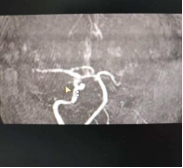

赶到时,初步检查提示“左侧颈内动脉闭塞性脑梗死”。县医院无法开展颈内动脉介入开通手术,必须立即转往西安。我一边快速完善术前评估、一边告知家属病情及转诊风险,一边联系我院介入团队做好术前准备,同时协调120救护车,全程陪同转诊。

12点,救护车顺利抵达我们医院,我陪同患者,对接我科介入团队,详细说明患者病情、转诊途中情况及前期处理措施,协助完善术前检查。12时24分,颈内动脉介入开通手术正式开始,随着我手中的导丝精准穿过血管闭塞段,取出长节段阻塞血栓,闭塞的血管逐渐恢复通畅,监护仪上的生命体征趋于平稳,我悬着的心终于落了下来。手术结束后,王爷爷家属红着眼眶再三道谢。所有的奔波与疲惫,都在这一刻有了最好的归宿。